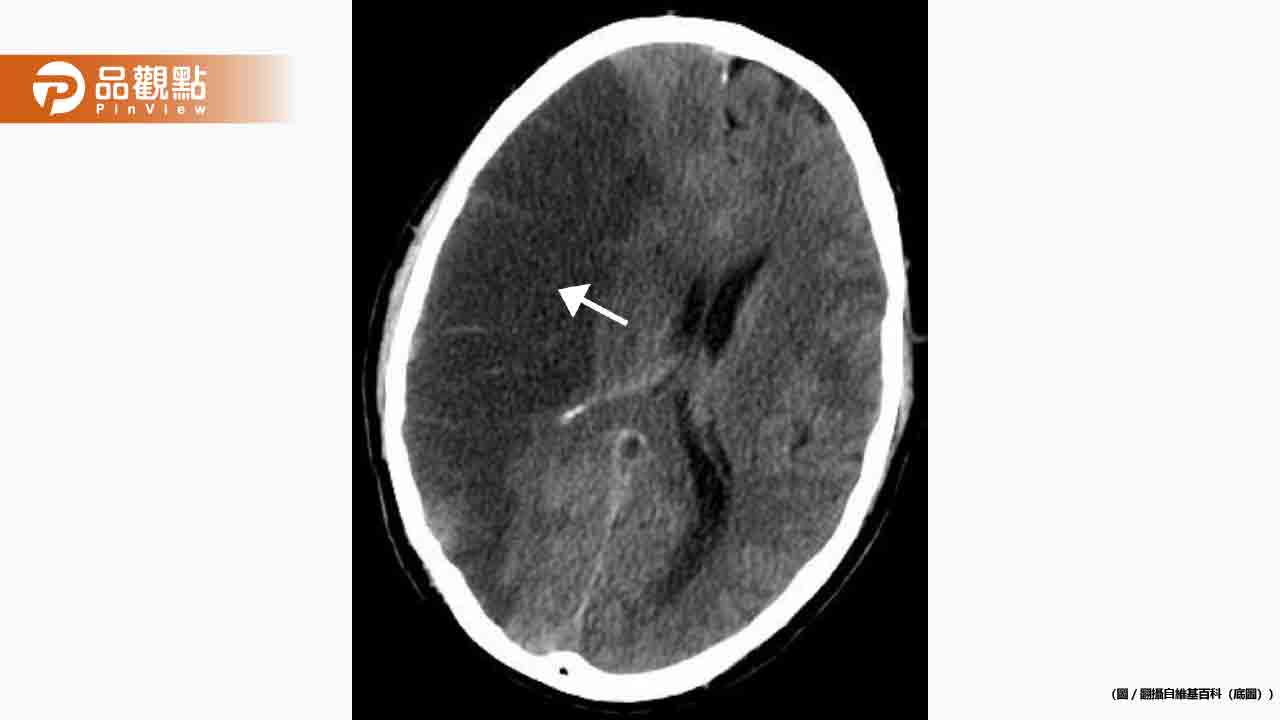

經過電腦斷層等檢查,男子被確診為腦幹中風,出血位置十分危險。為了控制病情,醫師將其收治於加護病房,並採用藥物治療,觀察是否需要進一步開刀取出血塊。